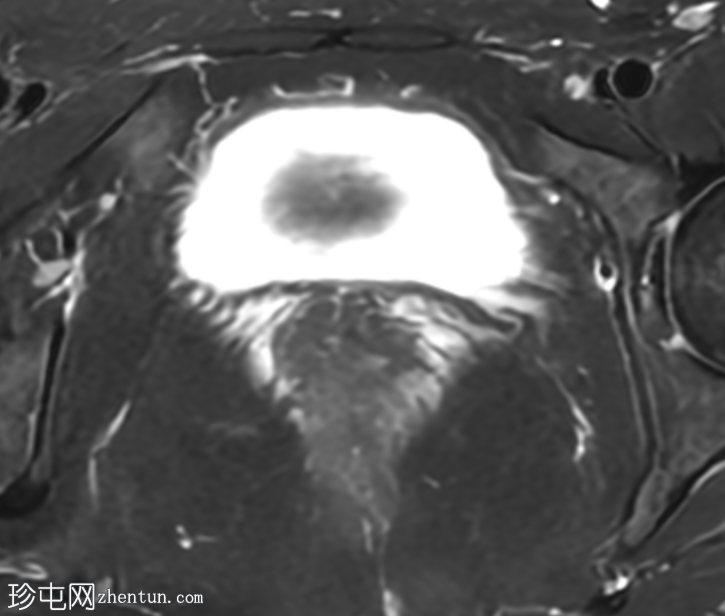

轴位T2加权像

脂肪抑制像

盆腔MRI显示右侧卵巢解剖位置可见一边界清晰的卵圆形肿块。该病灶由囊性和实性成分组成。囊性部分壁薄,在T2加权像上呈均匀高信号,在T1加权脂肪抑制序列上呈低信号,无对比剂增强。该实性成分的信号特征与正常卵巢组织相似,DWI成像未见扩散受限,静脉注射造影剂后未见异常强化。

此外,在子宫左侧壁可见一管状薄壁囊性结构,延伸至同侧髂外血管,末端呈盲端。该结构在T2加权像上呈均匀高信号,在T1加权脂肪抑制序列上呈低信号,且无造影剂强化。

本例中,盆腔MRI显示,患者右侧卵巢解剖位置存在一个边界清晰的附件肿块,该患者有20年前行双侧输卵管卵巢切除术的病史。该病灶包含囊性和实性成分,其中实性部分表现出与正常卵巢组织相似的信号特征。无扩散受限和无可疑的增强扫描强化提示排除恶性病变。这些影像学特征结合相关的手术史进行解读,符合残留卵巢组织的特征,支持卵巢残留综合征的诊断。此外,还发现对侧子宫左侧延伸出一个管状薄壁囊性结构,末端呈盲端。其形态、信号特征和无强化表现符合输卵管残端或输卵管残端积水,这是输卵管切除术后常见的术后表现。附件残余的存在进一步支持术后病因,而非原发性妇科肿瘤